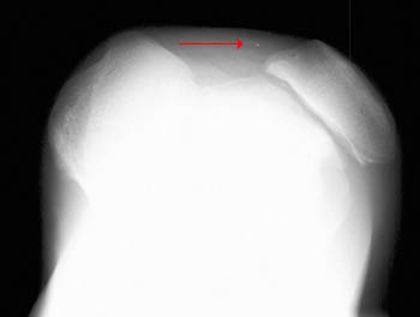

髌骨骨折

疼痛科怎么理疗疼痛科医生、康复理疗科医生、针刀针灸医生应掌握的常见骨科疾病X光片_https://www.jmylbn.com_新闻资讯_第33张

髌骨脱位